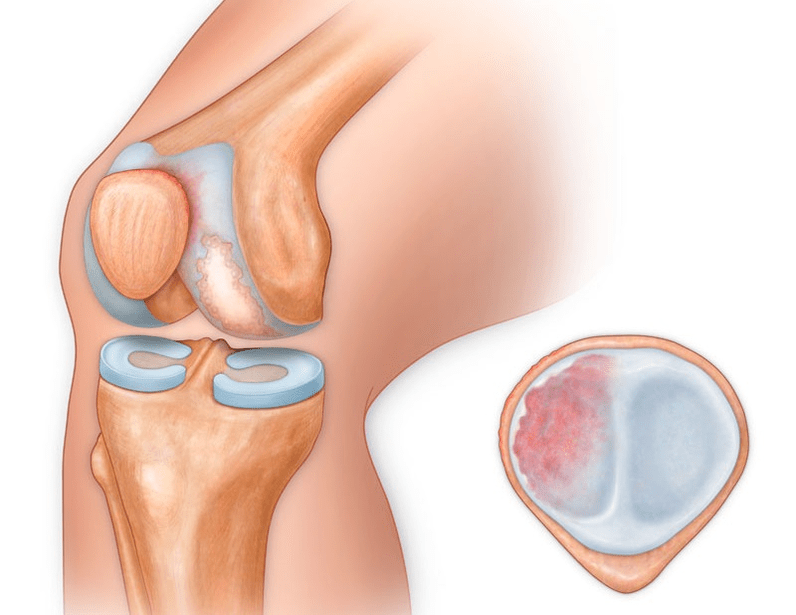

Oltre alla parte interna o esterna del ginocchio, l'artrosi può interessare anche le superfici tra la rotula e il solco intercondiloideo del femore. Questa opzione è chiamata artrosi femoro-rotulea.

La sua causa è solitamente una sublussazione, frattura o lateralizzazione della rotula.

Nella seconda fase, lo strato cartilagineo diventa nettamente più sottile e in alcuni punti è completamente assente. Gli osteofiti compaiono lungo i bordi delle superfici articolari. Le caratteristiche qualitative e quantitative del liquido sinoviale dell'articolazione cambiano: diventa più denso, più viscoso, il che porta ad un deterioramento delle sue proprietà nutrizionali e lubrificanti. Il dolore è più prolungato e intenso e spesso si sente uno scricchiolio durante il movimento. È presente una limitazione lieve o moderata del movimento e una leggera deformazione dell'articolazione. L'assunzione di analgesici aiuta ad alleviare il dolore.